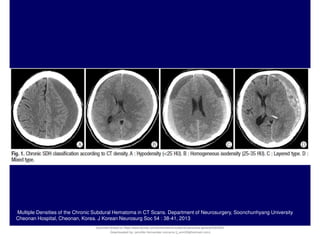

Multiple Densities of the Chronic Subdural Hematoma in CT Scans. Department of Neurosurgery, Soonchunhyang University

Cheonan Hospital, Cheonan, Korea. J Korean Neurosurg Soc 54 : 38-41, 2013